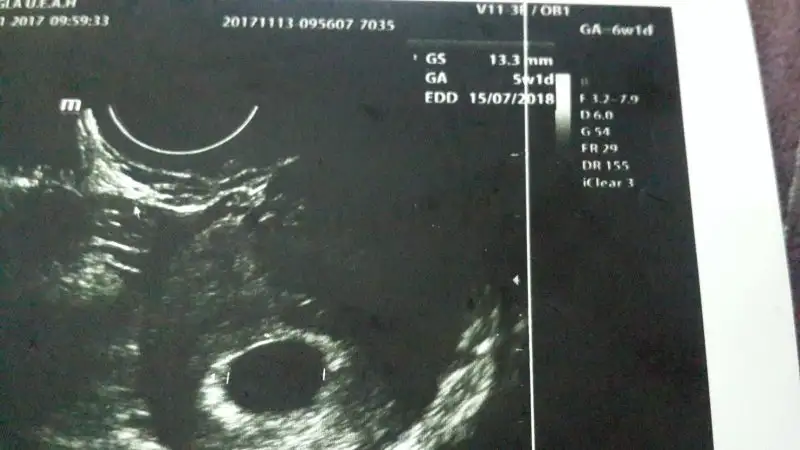

Canım sen doktora yolk sacı sordun mu ki genelde söylemiyorlar eğer resim yüklersen bi bakalım var mıBirde sizde yolk sac göründümu bende oda görünmüyor

Sormadım canim o da söylemediCanım sen doktora yolk sacı sordun mu ki genelde söylemiyorlar eğer resim yüklersen bi bakalım var mı

Belki de vardır da söyleme gereği duymamıştır aksi durum olsa söylerdi canm kesenin içinde nokta gibi birşey var mıSormadım canim o da söylemedi

Ultrason kağıdın var mı canımÇok teşekkür ederim arkadaşım içimi rahatlattin bende olumlu düşünüyorum inşallah olumlu olur hepimiz için mutlu hamilelik olsun

Yükleme yapamadım canım suan uğraşıyorumUltrason kağıdın var mı canım

Normal kese iste gayette guzel